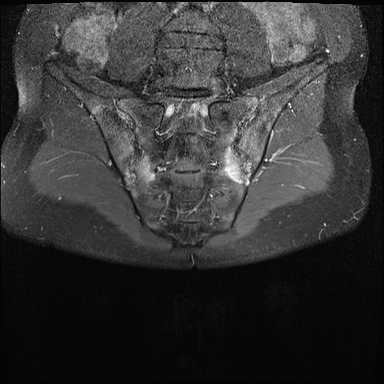

MRI

MRI chuỗi xung T1W sau tiêm thuốc tương phản từ của cùng bệnh nhân cho thấy bờ khớp cùng chậu không đều do bào mòn.

Có ngấm thuốc ở xương dưới sụn và phù nề tủy xương.

Không có tràn dịch khớp.

Thuốc tương phản từ tiêm tĩnh mạch không nhất thiết phải sử dụng để chẩn đoán viêm khớp cùng chậu.

Cuộn qua các hình ảnh MRI và so sánh với các dấu hiệu trên X-quang (hình ảnh cuối cùng).